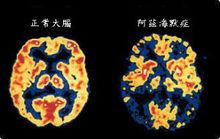

阿茲海默的父親是家鄉的一名公證人。阿茲海默先後進入柏林阿沙芬堡、蒂賓根大學和維爾茨堡大學。1887年,他在維爾茨堡大學獲得醫學學位。次年,他花了5個月時間幫助一位精神病女患者,然後進入法蘭克福市立精神病院。EmilSioli擔任精神病院院長(1852年-1922年),另一位神經科醫師尼梭(1860年-1919年)與阿茲海默共事。阿茲海默後來在腦病理學方面的許多工作使用了尼梭的組織學的銀黃著色方法。阿茲海默與人一同創辦出版雜誌 Zeitschriftfürdiegesamte Neurologieund Psychiatrie。正常與異常大腦比較 1901年,阿茲海默在法蘭克福精神病院觀察了一位患者D夫人,這位51歲的患者有奇怪的行為症狀,喪失了短時記憶。在以後數年中這位患者困擾了他。1906年4月,D夫人去世,阿茲海默將病歷和腦送往他工作的慕尼黑克雷佩林實驗室。2位義大利醫生和他一起工作,他使用著色技術鑑定澱粉和神經原纖維混亂。1906年11月3日,進行了老年痴呆症首次病理學和臨床症狀演說。

在病理學上顯示出腦組織萎縮、大腦皮質出現老年斑等現象。研究發現老年斑是β澱粉樣蛋白的沉積所造成。從髄液將腦內β澱粉樣蛋白進行定量控制的工具現在正在實用化研發階段。但是β澱粉樣蛋白是否為本症的直接原因,或者是患病後呈現出的結果,現在還沒有定論。